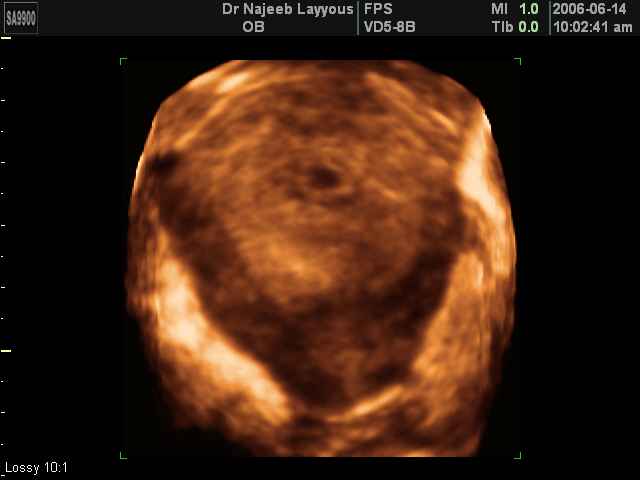

- 3D Photos Ecographie du Premier Trimestre

3D Photos Ecographie du Premier Trimestre (Photos d’échographie de tôt grossesse)| Dr N Layyous